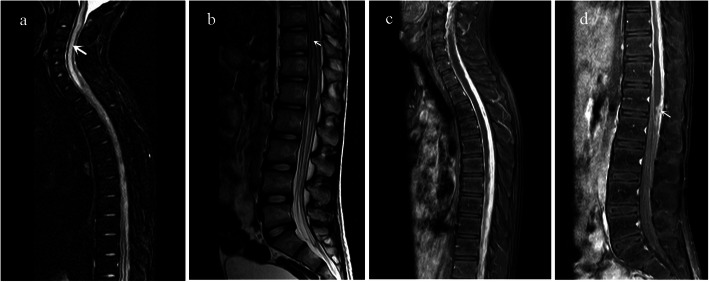

The patient was diagnosed with pulmonary TB and TBM and commenced on standard anti-tubercular therapy (isoniazid, rifampicin, pyrazinamide and ethambutol) with dexamethasone 0.6 mg/kg.d. In the following days, the patient became conscious and oriented, and experienced no recurrence of seizure or vomiting. Other symptoms including fever and headache were gradually relieved. However, seventeen days after treatment, he developed right upper quadrant pain and lumbodorsal pain, and thereafter, he developed spastic paraplegia of the lower limbs with fecal and urinary retention. On examination, there was motor weakness in the lower extremity (manual muscle testing assessed 1/5) as well as impaired sensation in right lower limb. Hypertonia and hyperreflexia were detected in the lower limbs. Repeat routine blood test and C-reactive protein were normal. MRI of the spine demonstrated generalized inflammation of spinal cord and meninges with enlarged syringomyelic cavities. Syrinx formation was exceptionally notable from C1 to T1 with the maximum width of 5.9 mm in the central canal of the cervical cord (Fig. 1a). T2-weighted images showed hyperintense signals within the spinal cord parenchyma (Fig. 1b). Contrast enhanced MRI demonstrated significant thickening and enhancement of the arachnoid, with narrow and even disappeared subarachnoid space (Fig. 1c). Hyperintense signals on T2 and isointense signals on T1-weighted images were shown in the subarachnoid space. There was atrophy of spinal cord from T6 to T8 (Figure 1c), and nodular enhancement of conus medullaris was shown (Fig. 1d).

Fig.

a Sagittal fat-suppressed T2-weighted MRI scan of the spine demonstrating notable dilation of the central canal of the cervical cord (Syrinx formation) from C1 to T1 (arrow). b Sagittal T2-weighted image of the spine demonstrating hyperintense signals within the lumbar cord (arrow) and conus medullaris. c Sagittal post-contrast T1-weighted image demonstrating extensive thickening and enhancement of the arachnoid, disappeared subarachnoid space, and atrophy of thoracic spinal cord. d Sagittal post-contrast T1-weighted image demonstrating nodular enhancement of conus medullaris (arrow)